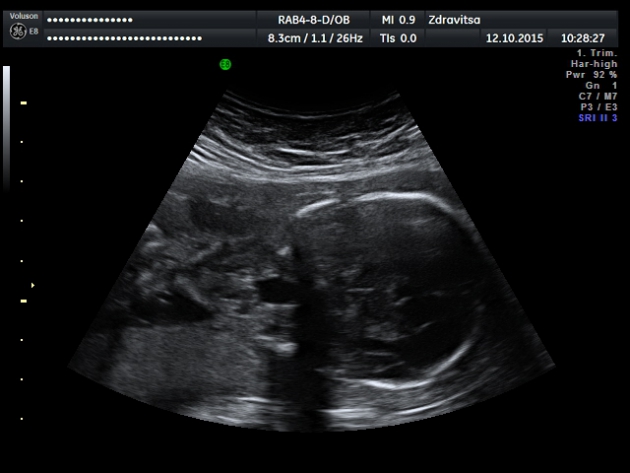

Медведев по этой патологии пишет: "По нашему мнению, наиболее действенной схемой диагностики атрезии пищевода является прямая визуализация пищевода плода в случаях обнаружения необъяснимого многоводия и микрогастрии или отсутствии эхотени желудка".

А так да, очень похоже на атрезию пищевода с трахеопищеводной фистулой.

В заключении по этому плоду в описательной части я указала, что данная структура связана с актом глотания плода. Может быть это и глотка, но что то она большая, пусть лучше будет еще одно мнение ,чем пропущу порок. И еще насторожило то ,что через два дня она вообще ни как не изменилась. Женщине все объяснила, в том числе, что это м.б и вариантом нормы.